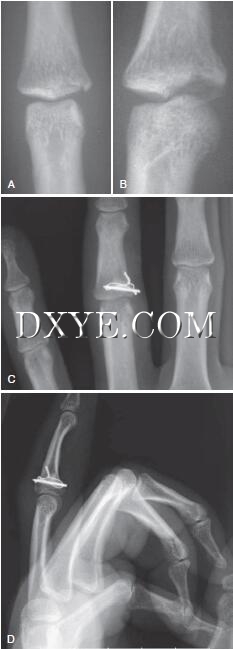

8.jpg

图 8.8  A,pilon近端指间关节损伤的远端延长,缩短和半脱位的前后位片。 B,牵引前同一损伤的侧位X线片。 C,闭合复位后的侧位X线片。